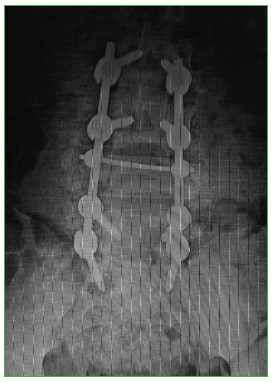

Se decide el tratamiento quirúrgico con abordaje posterior lumbosacro, reducción, descompresión posterolateral directa por técnica tipo eggshell y artrodesis lumbosacra larga L2-S1 (Figuras 11 y 12).

Figura 11.

Caso 2. Control radiográfico posoperatorio (frente).

Figura 12.

Caso 2. Control radiográfico posoperatorio (perfil).

El paciente evoluciona favorablemente, con recuperación neurológica completa. Se corrige la cifosis segmentaria con medición radiográfica a los seis meses de la cirugía adecuada (Cobb L3-L5 25°, lordosis lumbar 39°, incidencia pelviana 40°, IP-LL 1°, inclinación de la pelvis 8°). En la Tabla, se resumen los resultados en función de la clasificación, el puntaje de la ASIA, el porcentaje de ocupación del canal, el porcentaje de colapso vertebral, la cifosis segmentaria L3-L5, la escala analógica visual a los seis meses de la cirugía y el índice de Oswestry a los seis meses.